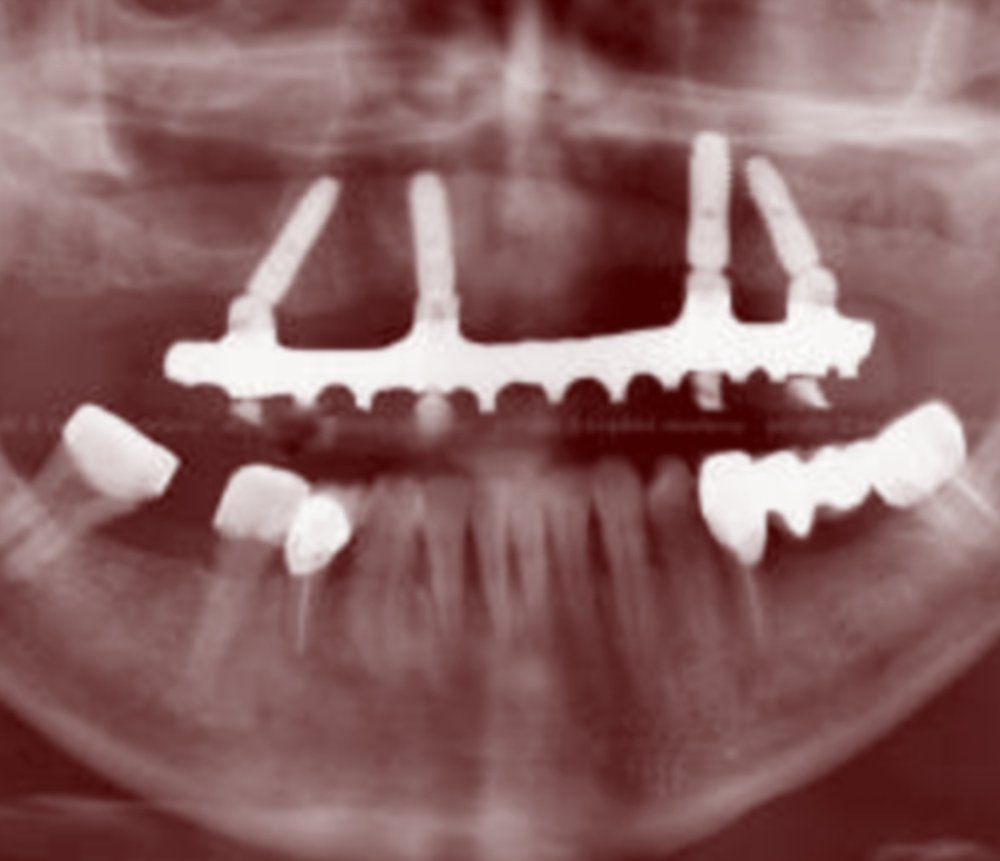

IMPLANT KIRIĞI

2018